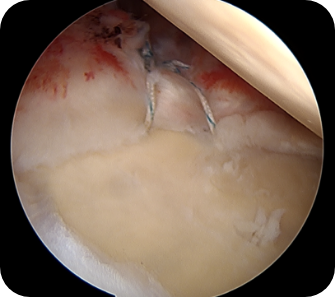

회전근개 질환, 오십견, 어깨 탈구 등 어깨 질환은 어깨의 통증과 고통을 야기합니다. 어깨 관절내시경 수술은 관절 질환이 의심되는 부위를 1cm 미만으로 최소절개한 뒤, 내시경 카메라와 수술 기구를 관절 내부에 삽입해 질환을 진단하고 치료하는 수술입니다. 화면을 통해 병변 부위를 직접 확인할 수 있어 손상 정도에 따라 파열된 힘줄을 봉합하거나 염증을 제거할 수 있습니다. CT나 MRI 등의 진단으로 잘 보이지 않던 곳까지 내시경을 삽입할 수 있어 적용 범위가 점점 넓어지고 있는 추세입니다.

- 파열된 어깨관절을 복구시킬 수 있습니다.